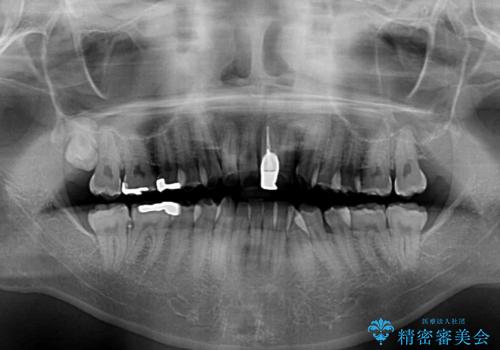

- 前歯のデコボコや八重歯を気にして来院された患者様です。

他院でワイヤー矯正を行うつもりでいらっしゃったそうですが、通院が難しくなったとのことで当院での治療を希望されて来院されました。

上下ともに歯列幅が狭く、その影響でデコボコになっていたため、ワイヤー装置を用いて歯列を側方に拡大しながら、デコボコを解消していくこととしました。